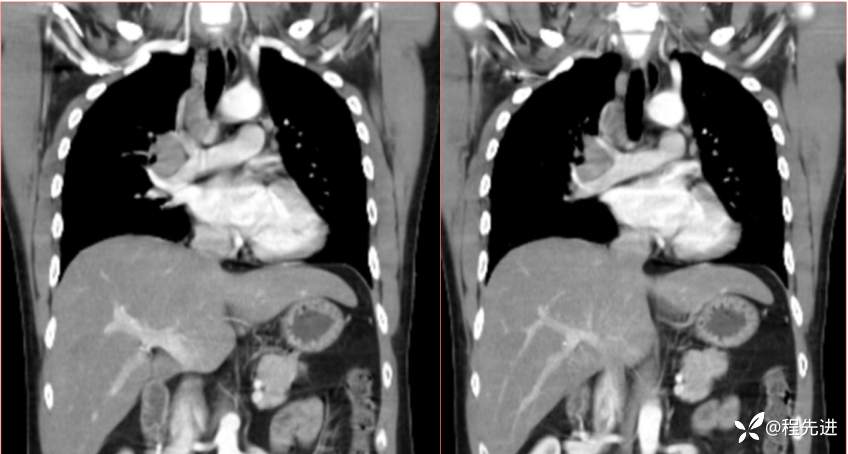

2023国庆特别精彩病例(一)|阵发性刺激性咳嗽,咳少量白色粘液痰1周|结果已公布

患者年龄:34岁

简要病史:患者一周前无明显诱因出现阵发性刺激性咳嗽,咳少量白色粘液痰,咳嗽无明显昼夜节律性,无发热、畏冷、寒战,无头痛、胸闷、胸痛,自行服药后 (具体不详) 症状无缓解,3天前外院胸片检查示右上病变

辅助检查:肺肿瘤标志物:神经元特异性烯醇化酶(NSE):35.72ng/ml(参考值0-16.3);非小细胞肺癌相关抗原211、胚抗原糖类抗原125、铁蛋白、鳞状细胞癌抗原未见异常